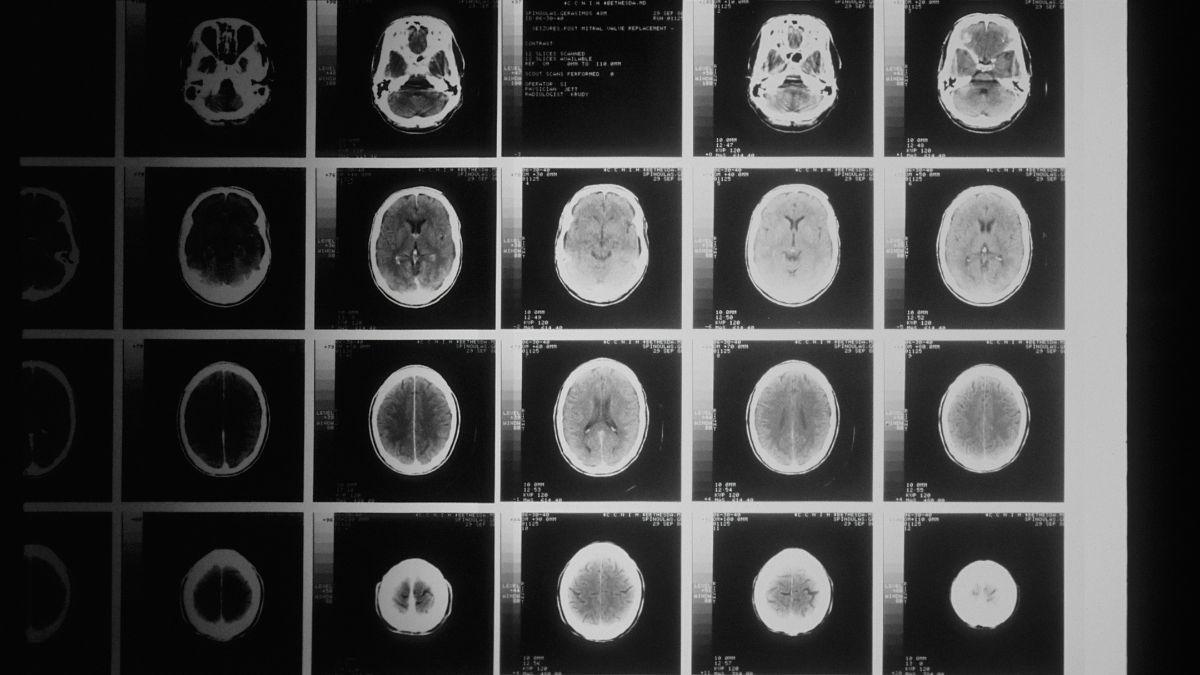

O diagnóstico baseia-se em critérios clínicos e suporta-se em exames como a ressonância magnética e a análise do líquido cefalorraquidiano, o fluido que envolve o cérebro e a medula espinal. A identificação precoce é importante para iniciar tratamento com fármacos “modificadores de doença”, que reduzem a frequência dos surtos e atrasam a progressão. Como multidisciplinar, a abordagem terapêutica pode incluir reabilitação física, gestão sintomática, seguimento psicológico e psiquiátrico.